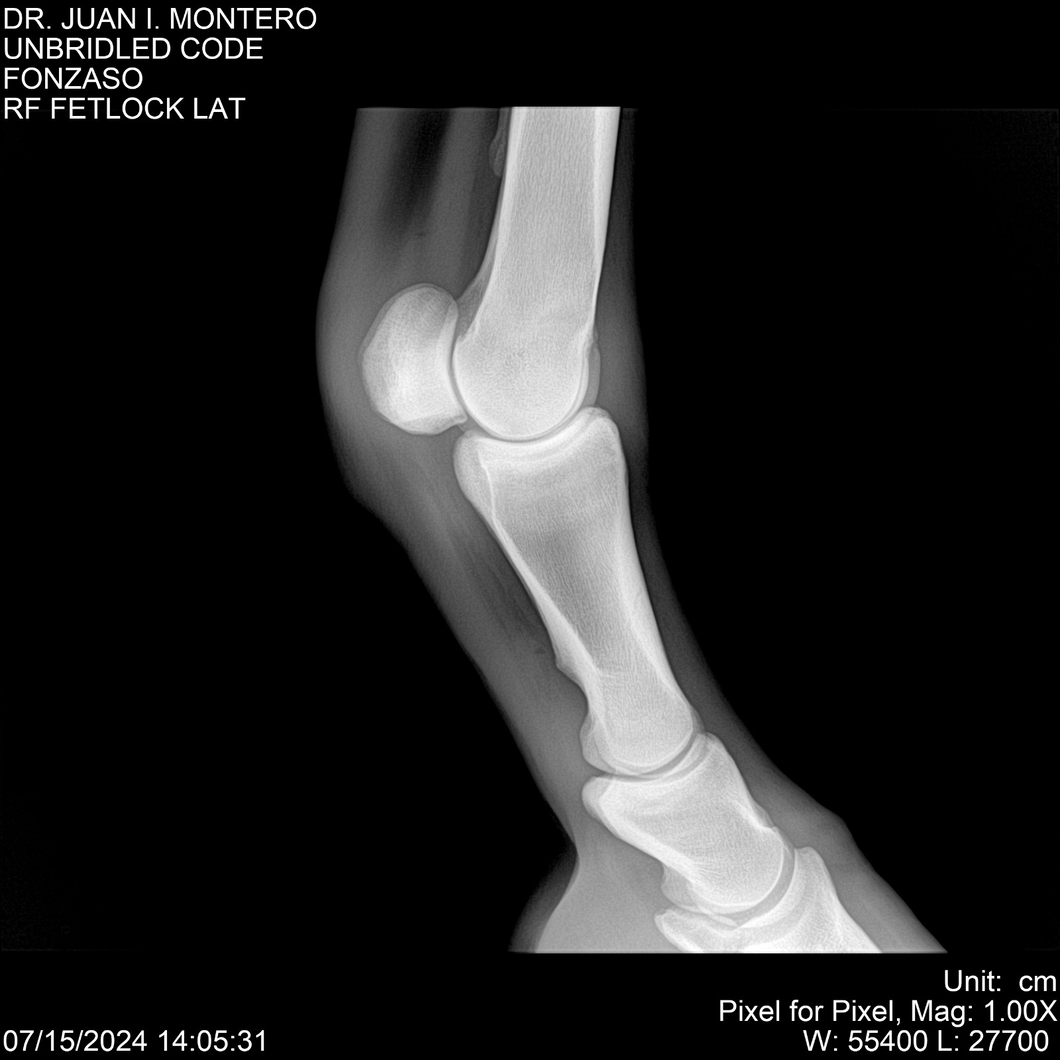

• Empresa: Abelenda N. R., Walter Hugo